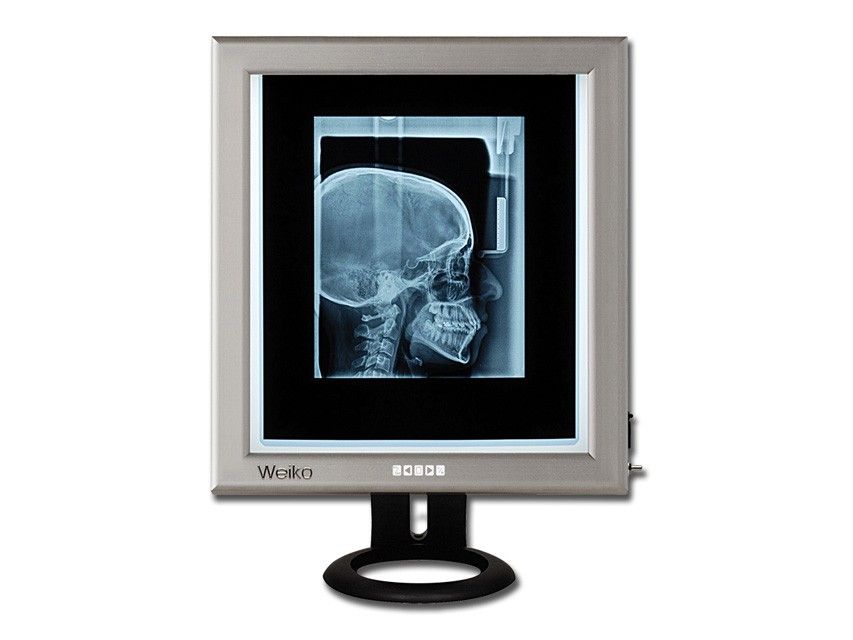

Negativoscopio Ultrapiatto Da Tavolo Led - 42 X 36 Cm